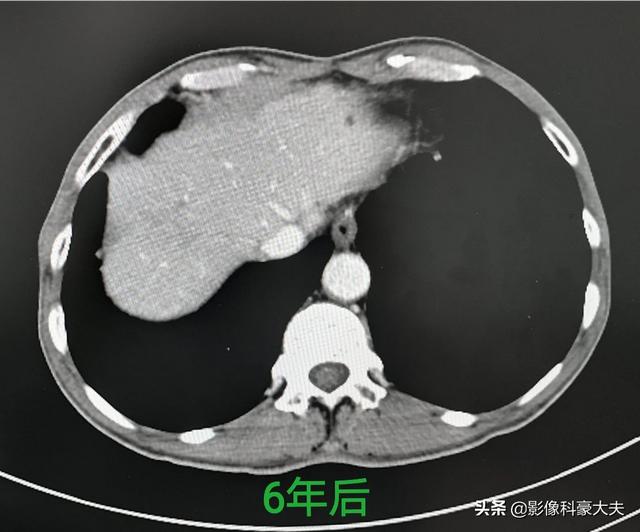

这是一位肝癌病人(曾经被称为癌症之王),发现比较早,没有发生远处转移和门静脉瘤栓,及时做了手术切除,今年已经是第6年了,没有复发:

如果发现比较晚,肿瘤已经发生了转移,常常就失去根治机会了。要承认:我们还没有完全攻克癌症,中晚期的病人大部分只能延长生存期,尽量减少痛苦。